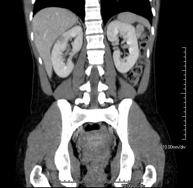

- Abdominal and pelvic CT

Diagnostic test that consists of obtaining high-definition anatomical images (bone structures, vascular structures, liver, pancreas, gallbladder, kidneys, adrenal glands, spleen, small and large intestine, bladder, uterus and ovaries, prostate and seminal vesicles, ureters, etc.) using CT (computed tomography) equipment. Most studies require the use of iodinated contrast.